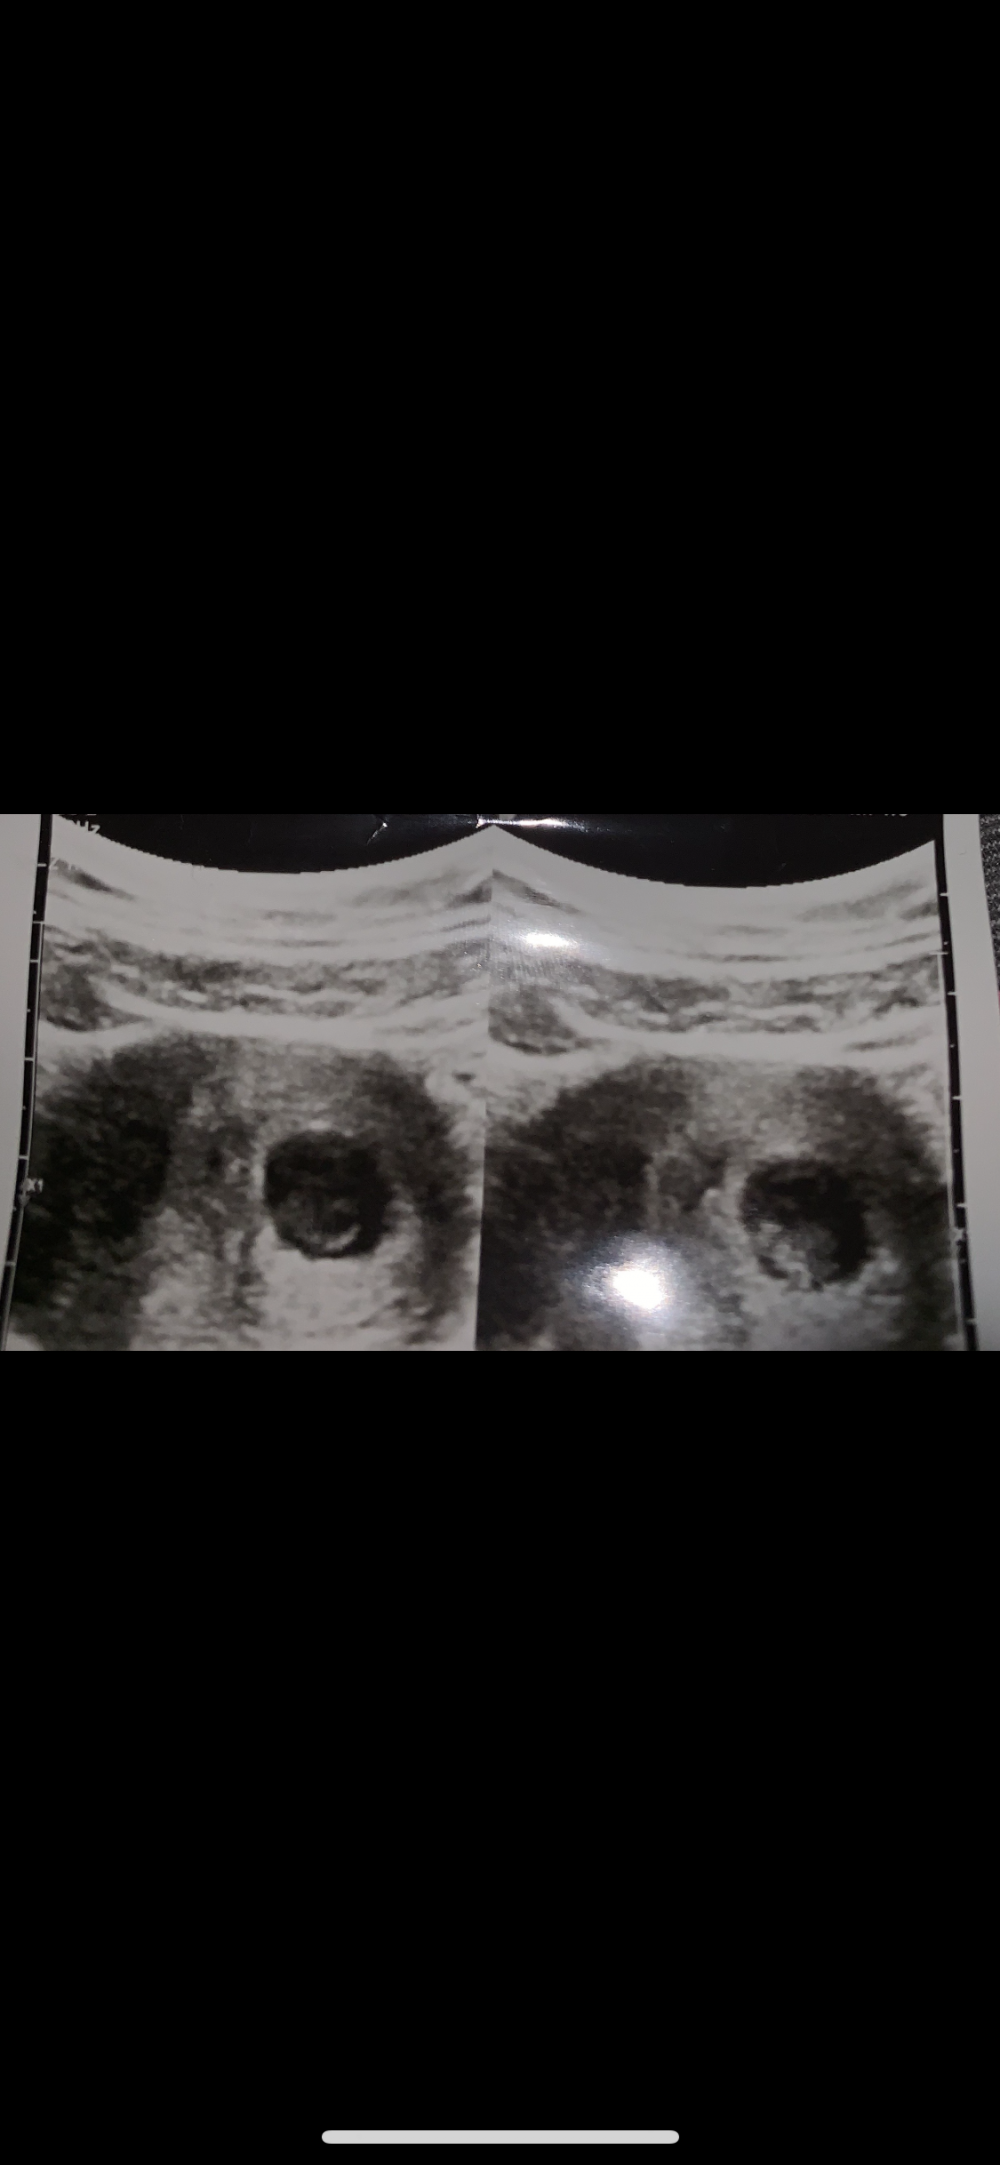

هذي صورة سوناري